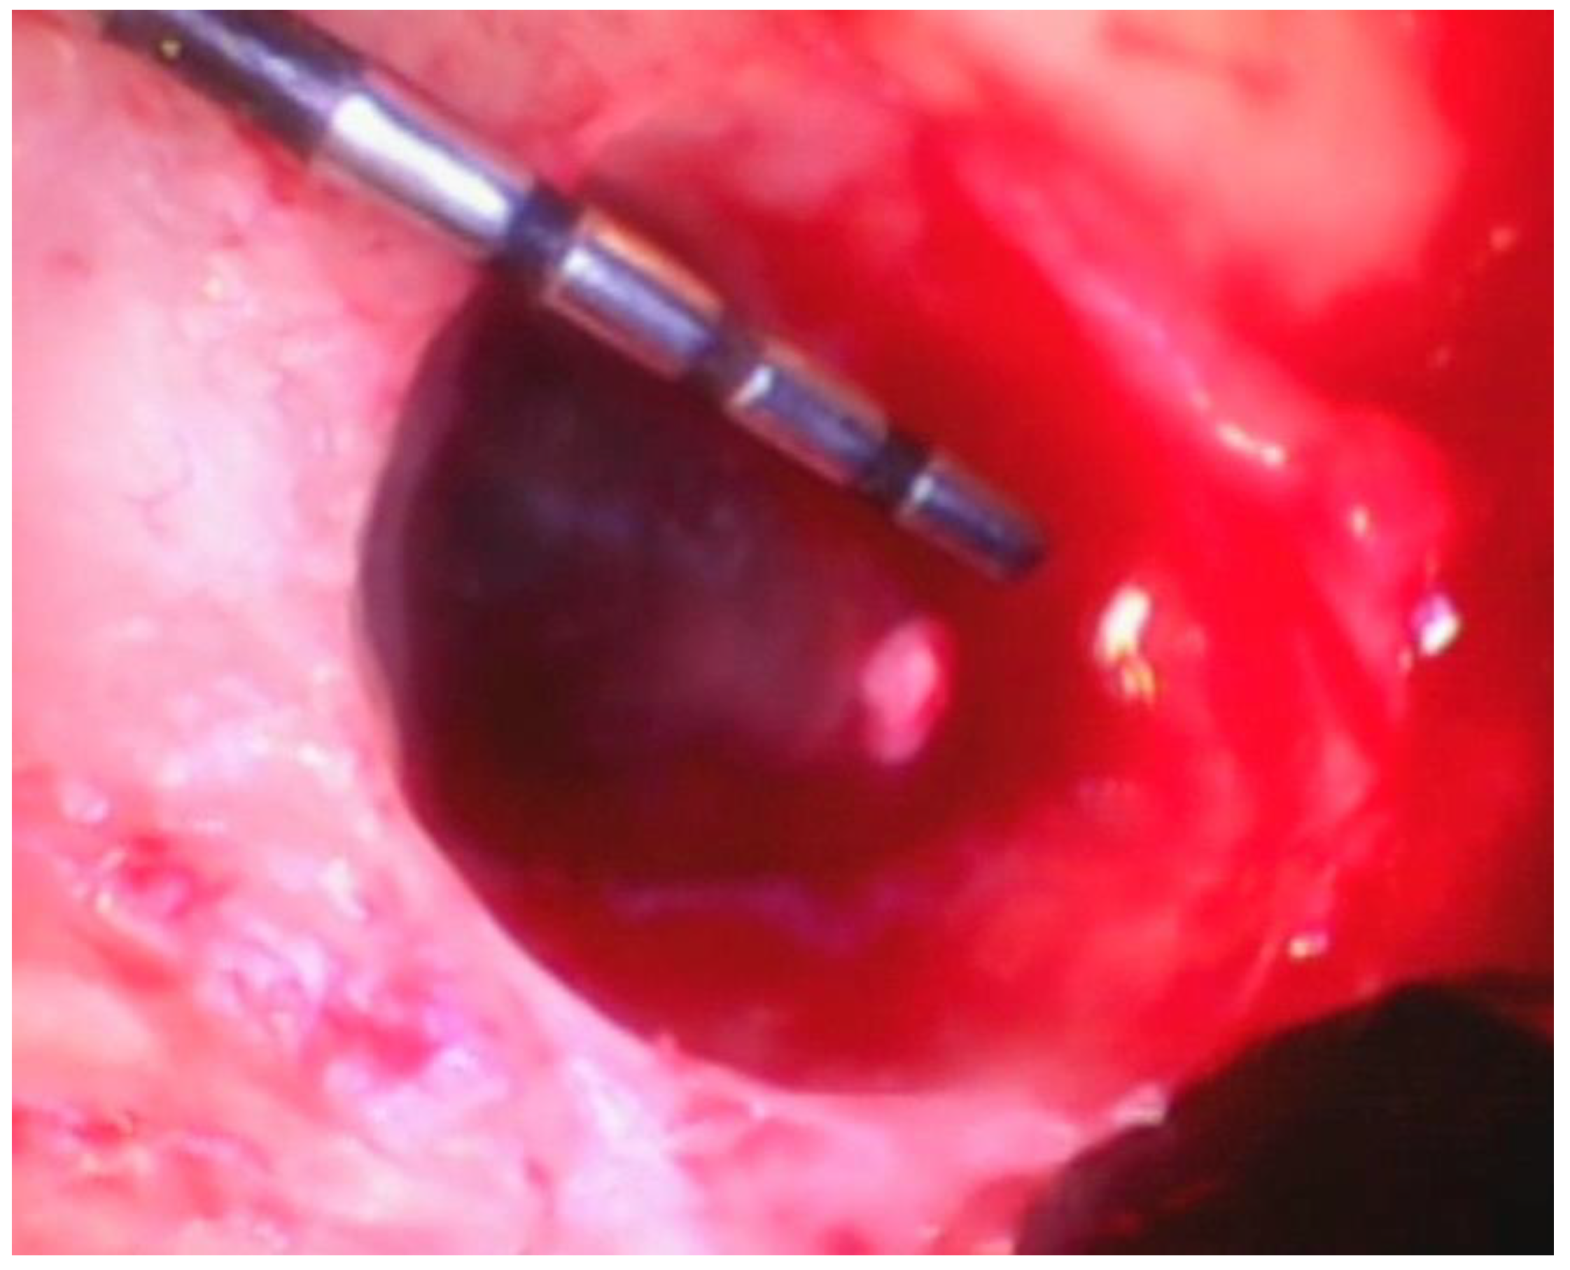

Debridement—Once incisions and the small split-thickness lingual flap have been made, the retractor on the handpiece of the videoscope is inserted, and light pressure is placed on the flap so that the defect can be visualized. Generally, there will be a significant amount of granulation tissue in the defect which must be removed. This is usually performed with a Younger-Goode curette that has been reduced in size by about one-third from its original size. This curette is used in an action similar to using an instrument to “spoon” out caries from a tooth. This action is more suitable for the small flaps of VMIS than the traditional “scaling” action used with surgical curettes. Once the granulation tissue has been removed, the root surfaces can be debrided of accretions and roughness. This is performed with a combination of ultrasonic instrumentation and hand instruments. The videoscope is used throughout the debridement process. When an ultrasonic scaler is used, there will be some transient blurring of the videoscope image due to water on the lens, but the air over the lens clears the image in a matter of seconds when the ultrasonic scaler is turned off. After mechanical debridement of the roots, they are dried with gauze and thoroughly inspected with the videoscope. The 20 to 40× magnification of the videoscope often reveals “micro-islands” of calculus and anatomical roughness on the root surface. 20 These can be removed with the use of EDTA (Prefgel, Straumann, USA), recommended by the manufacturer for the biomodification of the root surface before using EMD. A fully debrided defect ready for bone grafting is shown in Figure 4.

Figure 4. A furcation defect that has been fully debrided and EDTA used to remove any micro-islands of calculus. This site is ready for bone grafting and enamel matrix derivative (EMD) treatment.